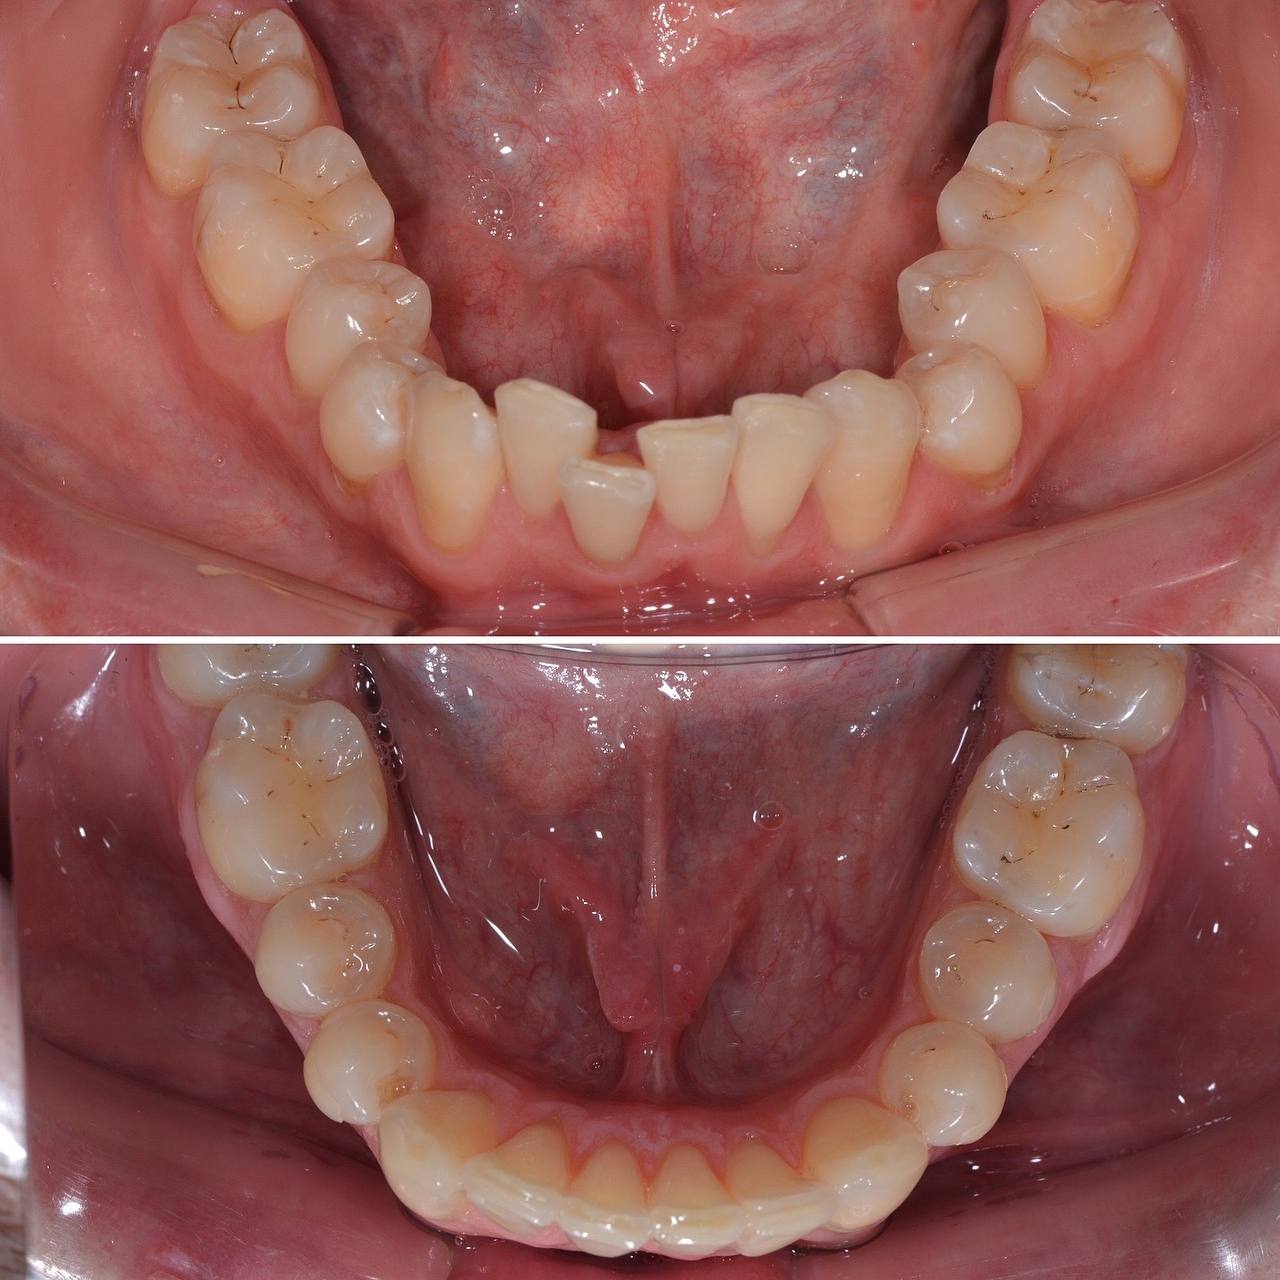

К нам с стоматологию обратился пациент с желанием сделать улыбку красивее. Лечением занимался стоматолог-ортодонт. Прикус и кривизну зубов исправляли при помощи элайнеров. Лечение заняло 12 месяцв. За это время было использовано 30 комплектов элайнеров.

Фото до и после лечения зубов элайнерами